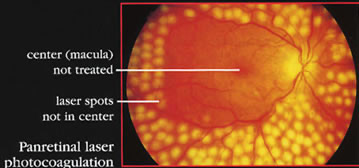

Our system offers ultra-wide imaging, with unsurpassed color and clarity, in high definition. This diagnostic tool is able to identify issues that evaded earlier systems. The images created by the camera can be separated to enhance the visual contrast in the various layers of the retina. This gives Dr. Soroudi the ability to identify diabetic retinopathy and investigate the periphery of the retina, where issues such as vascular leakage or other blood vessel-related problems can be seen clearly. This imaging system allows Dr. Soroudi to plan the ideal treatment for each individual client.